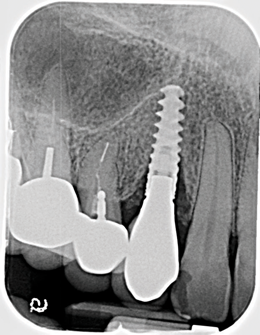

Fig 11. Pretreatment radiograph demonstrating bone loss on the mandibular right first molar.

Figure 11

Based on clinical and radiographic examination of the area, the patient was diagnosed with moderate peri-implantitis subcategory A (Figure 10 and Figure 11).19 Pocket depths at this implant ranged up to 9 mm. A surgical approach was planned that included implantoplasty and guided bone regeneration.